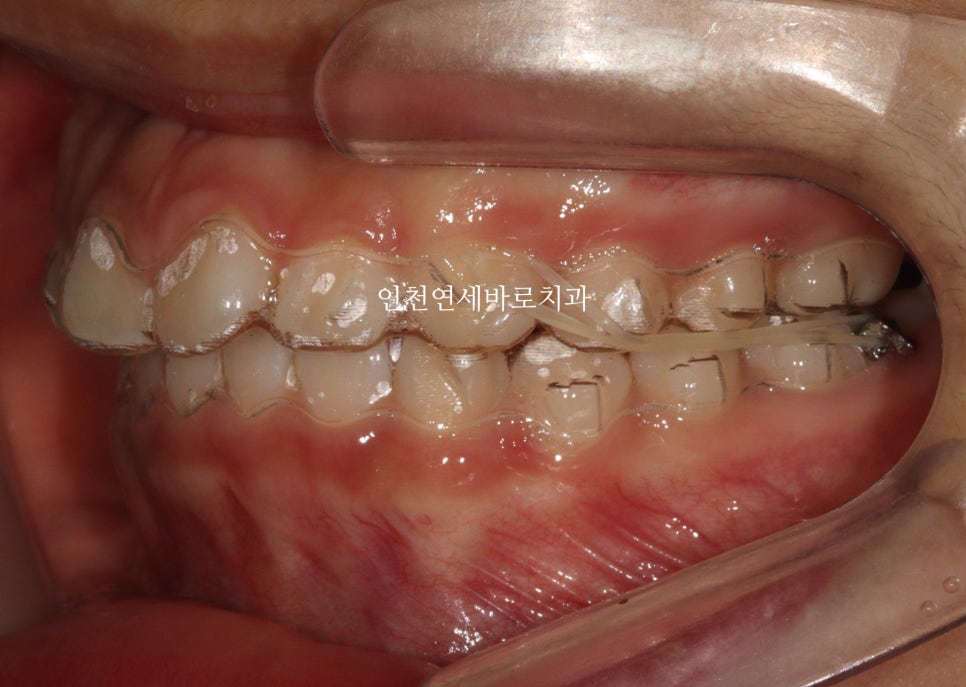

환자 초기 상태

인천연세바로치과에 온 환자아이입니다.

앞니가 튀어나와있고, 삐뚤삐뚤, 그리고

#과개교합

도 있는 아이었습니다.